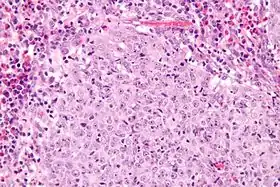

عن طريق فحص نسيج الورم باستخدام عينة، تظهر تحت الميكروسكوب بسيتوبلازم يشبه الزجاج مليء برشيح لمفي من الخلايا الحمضية (خلية حمضية) وكثيرة الانقسام الميتوزي، وباستخدام صبغة شيفحمض البيروديك [الإنجليزية] يظهر الغشاء الخلوي.[4]

صورة مجهرية سرطانة زجاجية الخلايا (منخفضة الوضوح)

صورة مجهرية سرطانة زجاجية الخلايا (عالية الوضوح)